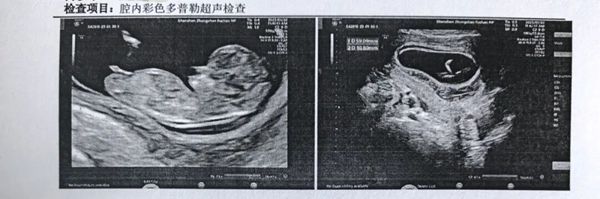

着床了。 后面产检一路绿灯,胎心胎芽都好好的。